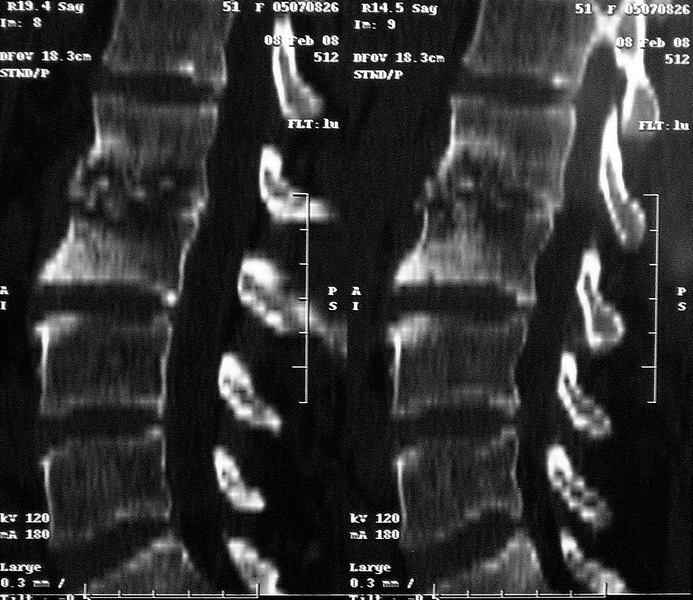

Re: Требуется телеконсультация Вертебролога

MRI через три недели